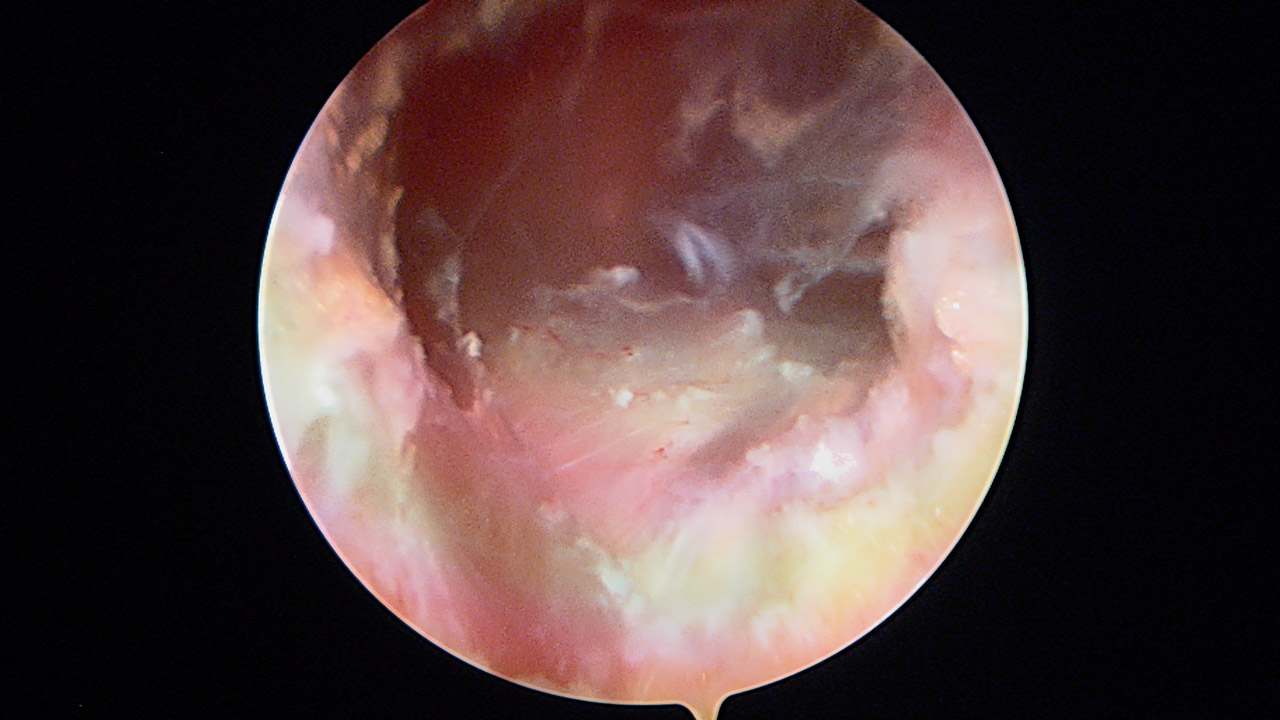

Presentamos una técnica quirúrgica artroscópica para los casos de inestabilidad traumática o atraumática de hombro, con hiperlaxitud multidireccional asociada, en los que hayan fracasado los tratamientos conservadores u otras técnicas quirúrgicas de plicatura capsular, y no presenten déficit óseo importante. Consiste en la plicatura del ligamento glenohumeral inferior (anteroinferior y posteroinferior) y la realización de una ligamentoplastia de refuerzo anterior artroscópica con aloinjerto en disposición transubescapular.

We present an arthroscopic surgical technique for cases of traumatic instability or atraumatic of the shoulder, with associated multidirectional hyperlaxity in which conservative treatments have failed, or other surgical techniques of plication capsular, and do not present major bone deficits. It consists of the plication of the lower glenohumeral ligament (anteroinferior and posteroinferior) and the accomplishment of an arthroscopic anterior reinforcement ligamentoplasty with allograft in a trans-scapular arrangement.